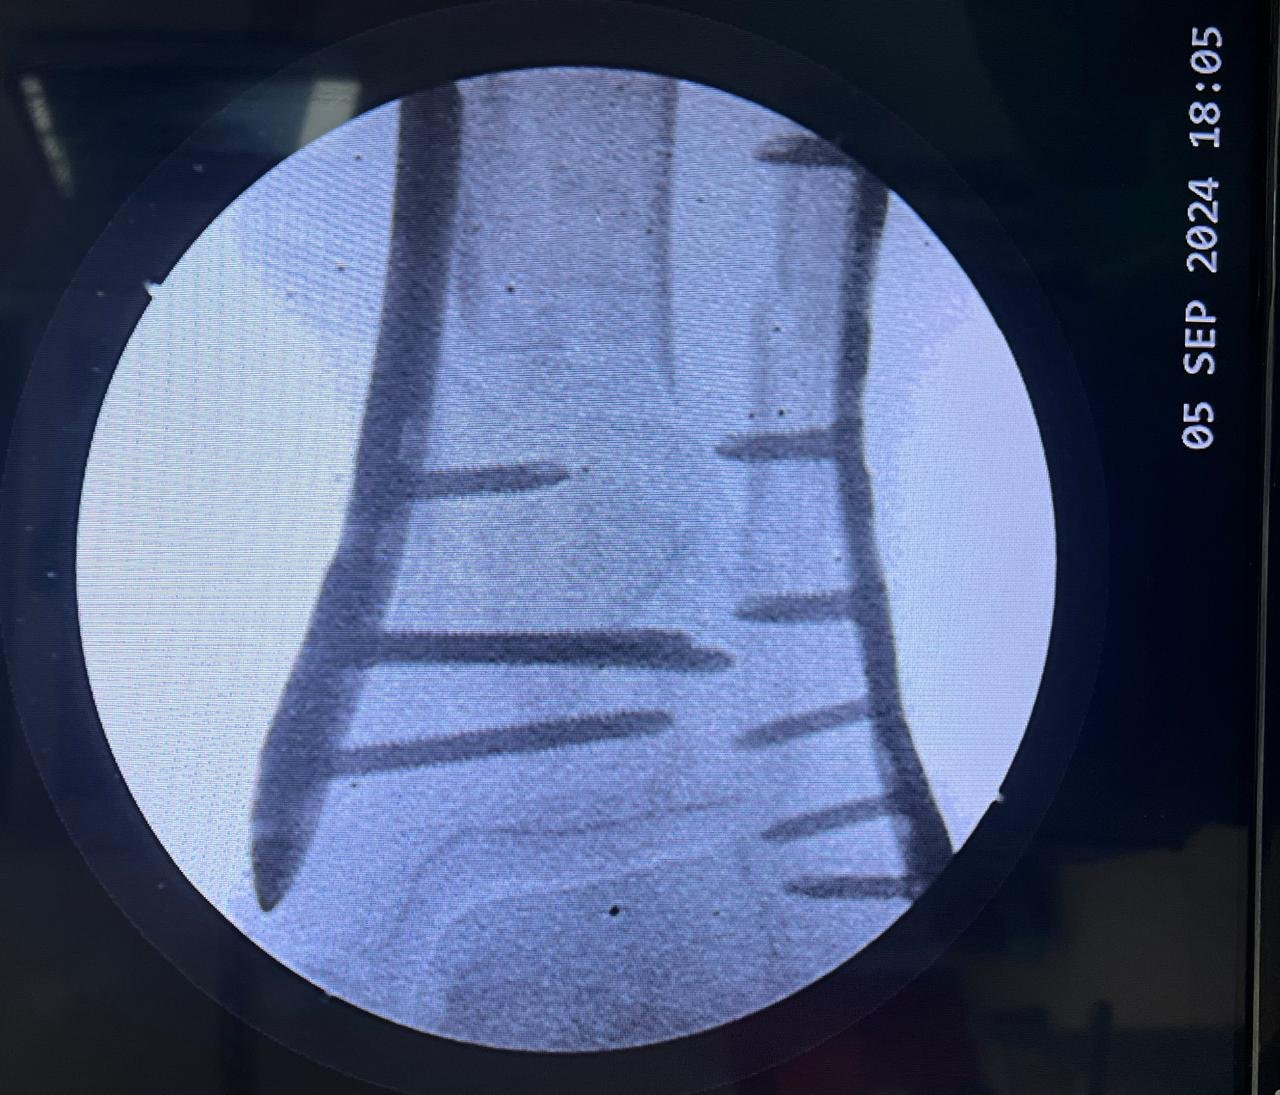

Pre op & postop X-ray compound fracture lower tibia

& fibula | Heal fracture pre & postop | Clavicle